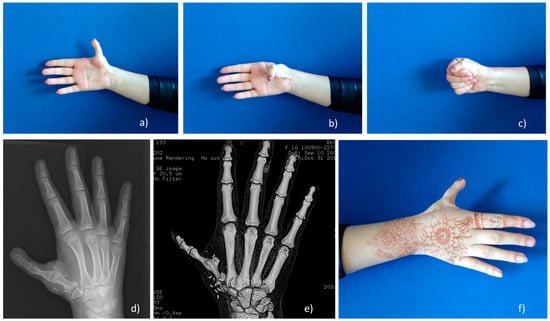

Figure 5. The second-toe-to-hand with MTP joint arthrodesis transplantation method outcome. (ac,f) functional and aesthetical outcome at 6-year follow-up; (d) X-ray with transplanted toe, neoCMC joint develops; (e) 3D CT view of stable, long 48 mm metacarpal bone (equal to contralateral side).

2.2.6. Second-Toe-To-Hand with MTP Joint Arthrodesis Transplantation Method

This method was developed in MC and has been used since 2010 (Figure 4 and Figure 5). The second-toe transplantation with MTP joint arthrodesis can be used for congenital absence of the thumb, such as in hypoplasia grade IIIb, IV or V cases, in which parents and patients decided to keep a five-digit hand. MTP joint arthrodesis is used to create a stable and long metacarpal bone, and the PIP joint becomes the MCP joint of the new thumb. Functional outcome results published by the authors showed similar functional results to pollicization functional outcomes, but aesthetical results were evaluated higher as five-digit hand is aesthetical more acceptable [8]. Second-toe-to-hand with MTP joint arthrodesis transplantation technique was successfully used to reconstruct grade IIIb thumb hypoplasia for a radial longitudinal deficiency (RLD) grade IV (Bayne and Klug classification [40,41]) patient with possible pinch and grasp movements [7].

The use of the second toe with MTP joint arthrodesis can be an alternative technique with a promising outcome. Simple MTP joint arthrodesis instead of MTP joint tendon rebalancing can provide stability and length for a reconstructed metacarpal bone [39]. The average operation time is 4 (4–4.05 h) h, which is much faster than the technique of Tu et al. [39], that requires an average of 8 (6–12 h) h. It seems that careful tendon rebalancing is a time-consuming procedure. A stable pseudo CMC joint is much more useful instead of stable fixation as modern touchscreen gadgets require mobility in the thumb and stability is not as important anymore as the number of laborers using hammers and axes are dwindling. The differences of the most common methods used for thumb hypoplasia grade IIIb–V reconstruction are listed in Table 1.